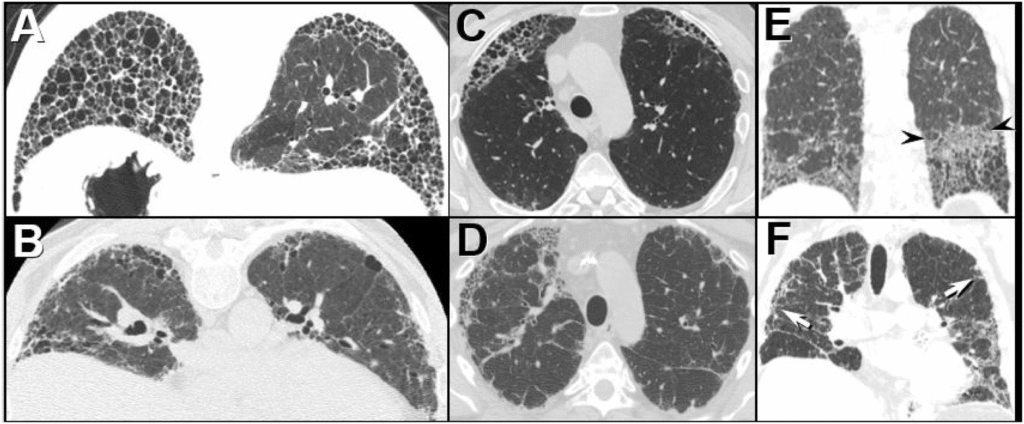

- HRCT (Goldstandard): „honigwabenartige“ Veränderungen (v. a. bei IPF)

| Idiopathische Lungenfibrose (IPF) | unklar (idiopathisch) | Belastungsdyspnoe, trockener Husten, Trommelschlegelfinger | HRCT: Honigwaben, basal, subpleural; Lufu: restriktiv | Antifibrotika(Pirfenidon, Nintedanib), evtl. Lungentransplantation | Respiratorische Insuffizienz, pulmonale Hypertonie |

| Exogen-allergische Alveolitis (EAA) | Inhalation organischer Antigene (Vögel, Schimmel → „Farmer-/Vogelhalter-Lunge“) | Dyspnoe, Husten, Fieber nach Exposition | HRCT: Milchglasinfiltrate, Noduli; Labor: AK gegen Antigen | Antigenkarenz, Glukokortikoide | Chronifizierung → Fibrose |